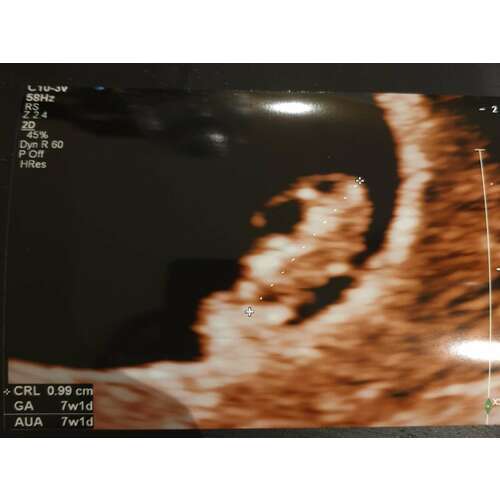

Ik zit bij embe, bij vroege miskraam vorig jaar waren ze heel meelevend en behulpzaam, dus ik dacht ik ga daar gewoon weer terug naar toe. Maandag eerste echo :)

Ik zit ook bij Partera. Gisteren het eerste intakegesprek gehad en maandag de eerste echo.